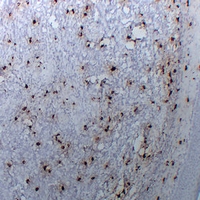

(Immunohistochemical analysis of Tryptase alpha/beta staining in human liomyoma formalin fixed paraffin embedded tissue section. The section was pre-treated using heat mediated antigen retrieval with sodium citrate buffer (pH 6.0). The section was then incubated with the antibody at room temperature and detected using an HRP conjugated compact polymer system. DAB was used as the chromogen. The section was then counterstained with haematoxylin and mounted with DPX.)